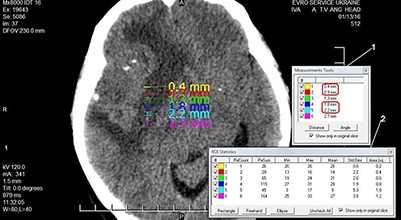

В іншої пацієнтки Ів., у якої поперечні зрізи головного мозку були виконані на тому ж апараті та за аналогічних умов, було отримано результати, подані на рисунку 2.

Отримані дані програмного визначення розміру пікселя, довжини та площі виділеної ділянки зображення, а також розрахункових значень розміру пікселя, довжини та площі зображення внесено до таблиці 2.

Кількість Пікселі (мм) Площа (мм2) розмір (програма) розмір (розрахунок) розмір (програма) розмір (розрахунок) 1 0,4 0,4 0,2 0,16 2 0,9 0,8 0,4 0,32 3 1,3 1,2 0,6 0,48 4 1,8 1,6 0,8 0,64 5 2,2 2,0 1,0 0,8 6 2,7 2,4 1,2 0,96

В іншої пацієнтки (рис. 2, табл. 2) отримано інші результати, але теж з відмінностями. Як видно з даних, наведених у таблицях, в обох випадках спостерігається некоректне визначення програмою «eFilm» розмірів пікселя, довжини виділеної ділянки зображення та її площі, значення яких перевіряли ручними арифметичними розрахунками.

У пацієнтки Ів. аналіз даних, наведених у таблиці 2, виявив системну похибку 10% щодо площі зображення пікселів та 11% – щодо розмірів пікселів. При цьому фізичні умови томографії обох хворих були однаковими. Загалом проведений непараметричний аналіз програмних та розрахункових даних щодо геометричних невизначеностей виявив похибку 8-15% (статистична значущість визначалася за порогом p<0,025) залежно від того, яка ділянка розглядається – у центрі чи на периферії.